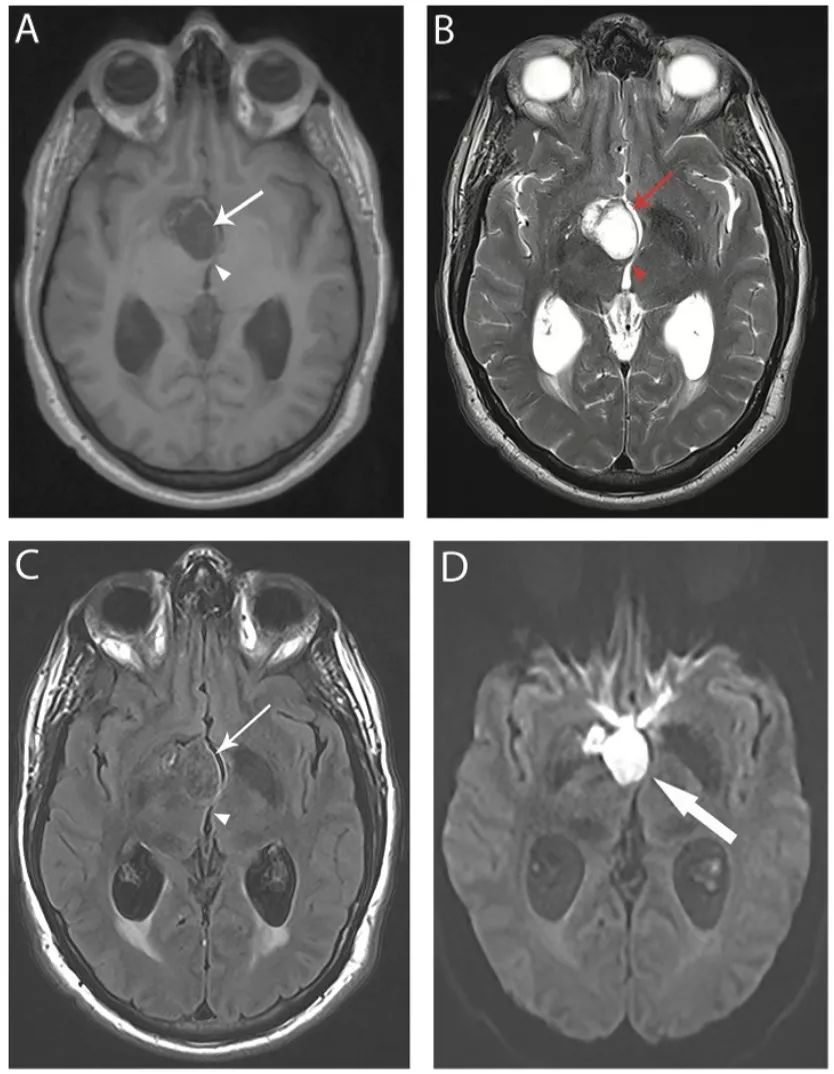

图20 脑囊虫病

轴位FLAIR(A)、增强T1IW像 (B)和冠状位增强T1WI(C)显示不同时期脑囊虫病的多发囊性病灶。囊泡期可见左额叶前部薄壁囊肿,囊内物质在FLAIR为低信号,无明显增强(楔形箭头);背外侧左额叶囊肿FLAIR高信号、增强后高信号(细箭头),为胶囊囊泡或神经囊尾蚴的颗粒状结节阶段。(C)上矢状窦相邻的两个囊肿(粗箭头)。